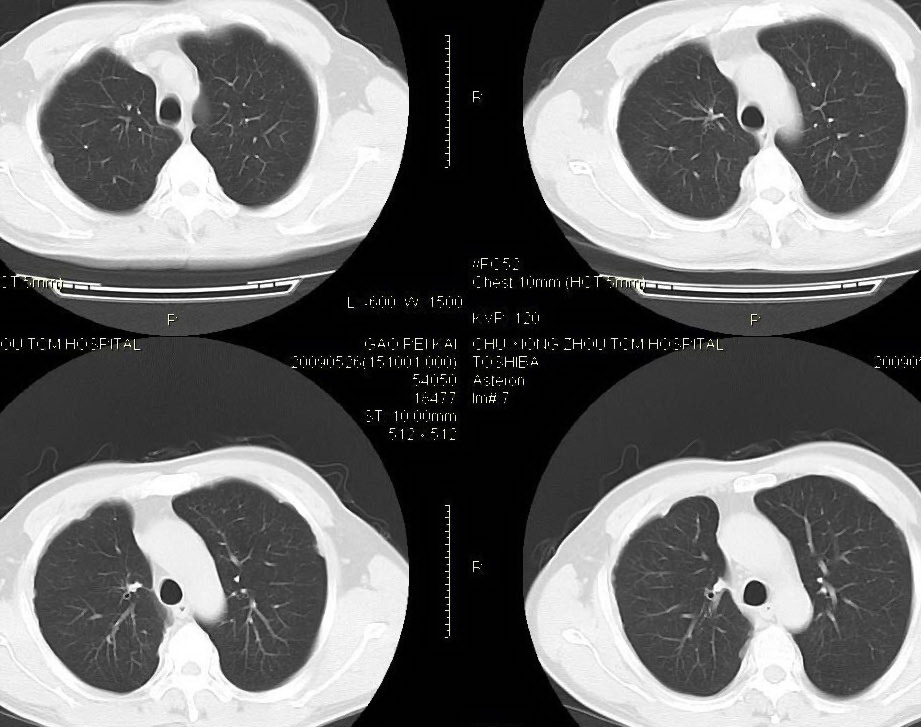

男,56岁,右侧腋窝下巨大软组织包块转移。欢迎讨论。

该病例为已经确诊的右侧恶性胸膜间皮瘤病例,有青石棉接触史,早期就是胸水,右侧胸壁“花边状改变”,心隔角区软组织阴影形成。近期右侧腋窝下巨大软组织包块,病检为转移瘤。图片没有完全考来,主要是给大家看一下胸膜间皮瘤的病例。,右侧

右侧腋窝下巨大软组织包块已经被切除后的ct片,该病例有多家医院较多的ct检查片。

右肺下叶节段性肺不张、右侧胸膜肥厚并包裹性积液。“右侧腋窝下巨大软组织包块转移?”就目前图片看,没见!请上传完整图像。

1)右肺中叶节段性肺不张。2)右肺中叶肺癌不排除。3)右侧胸膜增厚。

右心膈角区一不规则肿块伴相邻胸膜不规则增厚,考虑胸膜间皮瘤(恶性)?右肺中叶内侧段肺癌?建议穿刺活检。